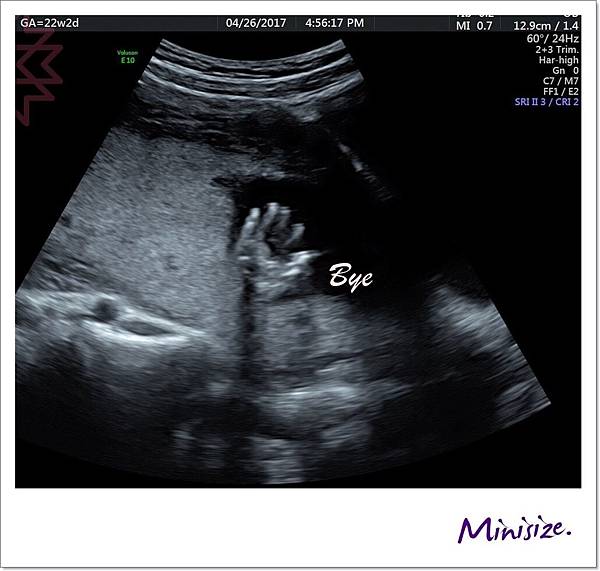

此時寶寶跟我們玩起遊戲來了

頑皮寶寶:手手、 臍帶 一起遮住臉臉不給你們看

寶寶:我累了

你們照太久 我先抱著腿腿入睡囉

超音波結束後

醫生會先至旁邊諮詢室等待

等我們都到齊後

電腦開啟報告再次解說此次高層次檢查結果

我們的Timo寶寶檢查數據都正常 很健康唷!